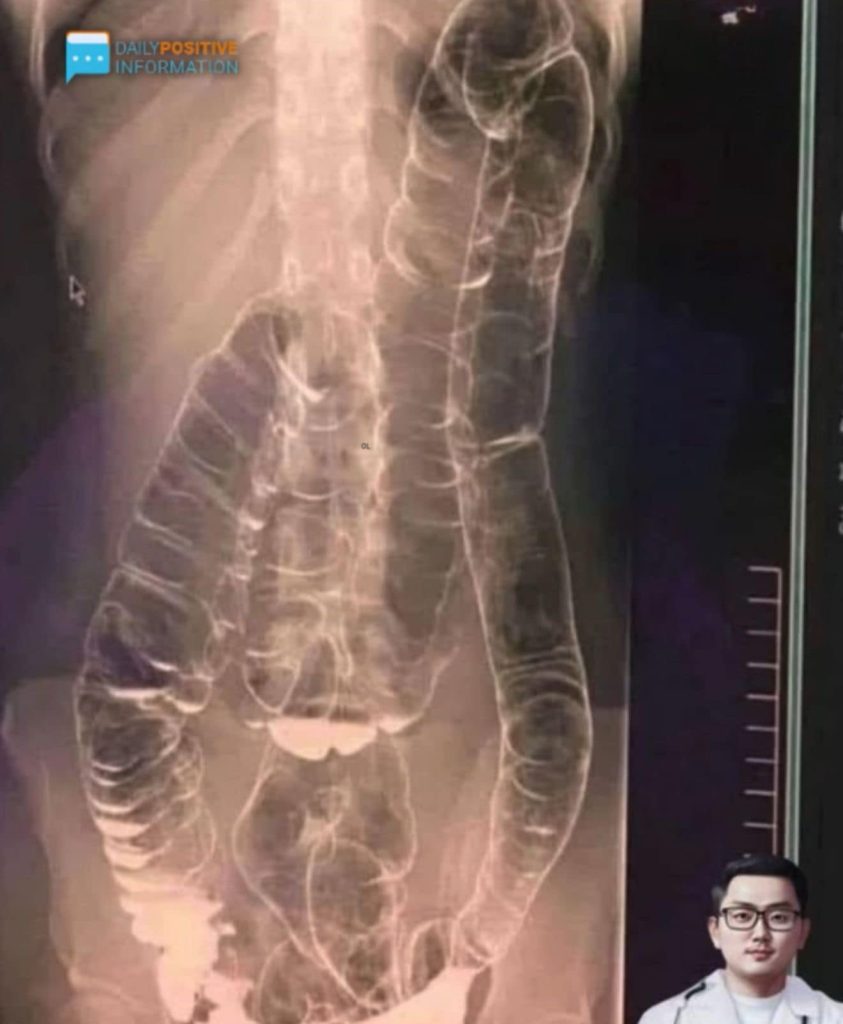

Constipation is often brushed off as a small inconvenience, but when it becomes chronic, it can turn into a serious health risk. In one alarming case, a young woman’s untreated constipation caused her colon to swell so severely that it pressed upward toward her chest, leaving her in severe pain. Long-term constipation isn’t just uncomfortable—it can trigger complications like toxin buildup in the body, painful hemorrhoids, anal tears, intestinal blockages, and may even raise the risk of colon cancer.